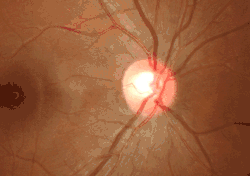

![]() The terminal portion of the optic nerve and its entrance into the eyeball, in horizontal section. | |

The optic disc is located 3 to 4 mm to the nasal side of the fovea. It is a vertical oval, with average dimensions of 1.76mm horizontally by 1.92mm vertically.[2] There is a central depression, of variable size, called the optic cup. This depression can be a variety of shapes from a shallow indentation to a bean pot—this shape can be significant for diagnosis of some retinal diseases.